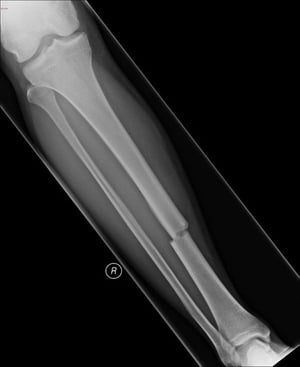

Diversi tipi di fratture

Frattura trasversale della diafisi della tibia

Questa frattura trasversale colpisce la parte mediale della diafisi della tibia.

Image courtesy of Danielle Campagne, MD.